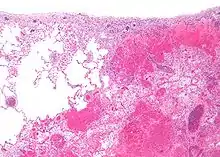

Infarctul (lat. infarctus) reprezintă moartea brutală și masivă a celulelor țesutului (necroză ireversibilă a unei părți a unui organ) cauzată de lipsa locală a oxigenului, din cauza unei obstrucții a arterei țesutului.[1] Procesul de formare a unui infarct se numește infarctizare, iar rezecția unui infarct se numește infarctectomie.[2]